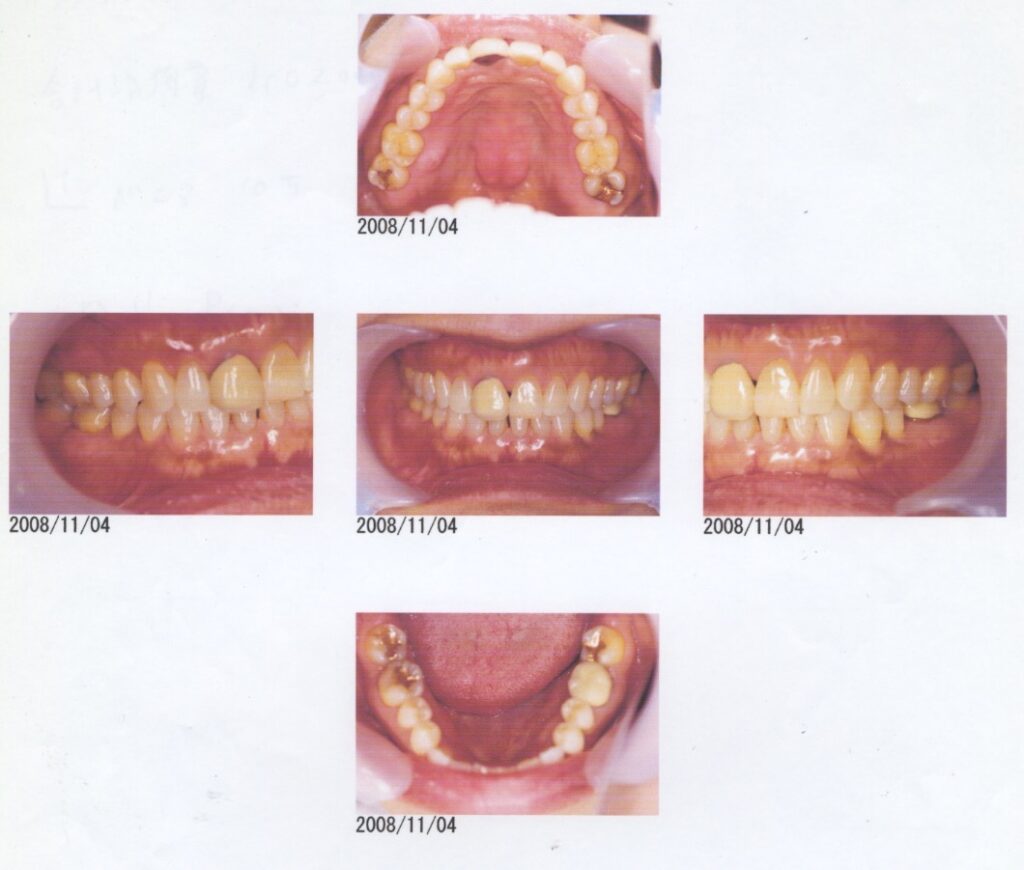

H20.11.4

56歳女性

打撲した上の前歯をインプラントに

- 8〜10年前から他の歯科医院にて治療を受けたが、見た目が良くない・噛めないとのことで再治療を希望された。アングルクラスⅠであった。右上前歯は小学生ののろ打撲。左下奥歯は歯根破折。